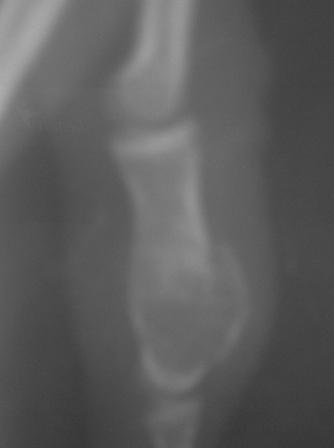

После Вашего послания сделал Р-граф. всей кисти, оказалось имеется патология 2 и 3 пястных костей!

Р-снимок прилагается.

С уважением Абдурашид.

Кликните для загрузки файла PICT0006.JPG